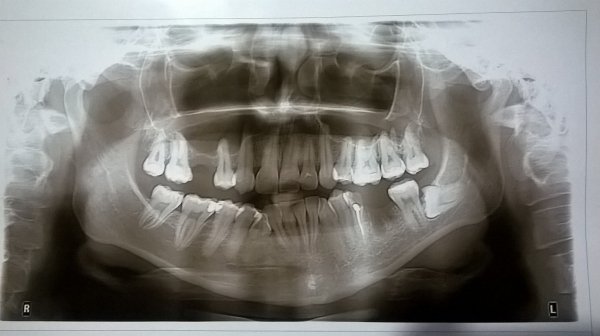

Примерно около полугода назад я потеряла передний зуб. В клинике мне в этот же день поставили пломбу, но я бы хотела что-нибудь более эстетичное и не темнеющее со временем.

Что Вы посоветуете? И на какую цену мне нужно рассчитывать? Врачи в этой клинике (где делали пломбу) отговаривают делать замену на что-то более стоящее, так как не видят в этом смысла. Но я хочу отбелить свои зубы, и чтобы потерянный зуб не слишком бросался в глаза.

Необходимо для начала заняться отбеливанием, а после восстановить зуб коронкой E-max, виниром или циркониевой коронкой. Вы совершенно правы, пломбой Вы не добьетесь идеального результата.